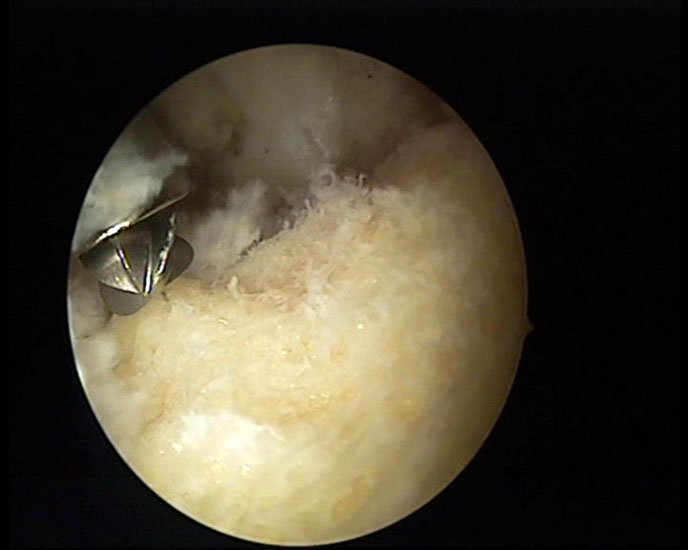

Abbildung 8, Video 3

Nach vollständiger Darstellung erfolgt die Resektion der Exostose mit einem Acromionizer von medial, wobei auch hier die geschlossene Seite des Arbeitsansatzes zum Schutz der Achillessehne nach dorsal ausgerichtet werden sollte. Verwendet werden können wahlweise Kugel-, Zapfen- oder Walzenansätze mit 3,5-5,5 mm Durchmesser. Ein kleinerer Durchmesser vereinfacht zwar das Handling im engen retrocalcanearen Raum, erfordert aber einen höheren zeitlichen Aufwand als die Verwendung einer höherkalibrigen Fräse. Der Knochenabrieb verstopft dünne Instrumente häufig und der Durchfluss der Spülflüssigkeit ist gering. Es hat sich bewährt, zwei verschiedene Größen bereitzuhalten und ggf. intraoperativ zu wechseln.